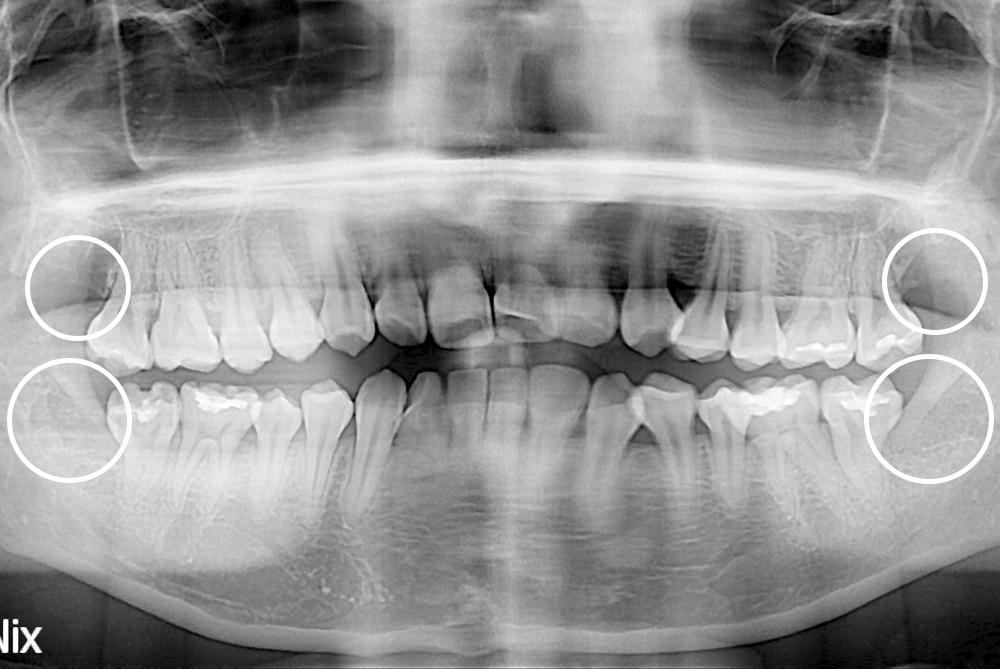

[사랑니] 매복 사랑니 발치

치료후 : 2019-06-19

세종치과는 구강악안면외과학 박사이신 원장님이 발치하는 치과입니다.